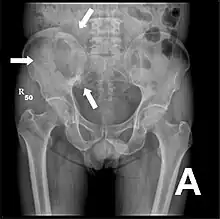

Par comparaison, scanner de métastases ostéolytiques dans l'os du crâne d'une patiente souffrant d'un cancer du sein. On distingue une ostéolyse plus grande sur le front, et plusieurs plus petites. Radio du bassin d'un patient atteint d'un carcinome de la prostate : multiples métastases ostéocondensantes, en particulier sur le sacrum, mais aussi sur l'ilion surtout gauche (à dr. sur l'image), sur la pointe de l'ischion gauche, et sur le fémur proximal gauche. On détecte à l'occasion une arthrose de hanche droite (à g. sur l'image).

Radio du bassin d'un patient atteint d'un carcinome de la prostate : multiples métastases ostéocondensantes, en particulier sur le sacrum, mais aussi sur l'ilion surtout gauche (à dr. sur l'image), sur la pointe de l'ischion gauche, et sur le fémur proximal gauche. On détecte à l'occasion une arthrose de hanche droite (à g. sur l'image). Radio du bassin avec métastases ostéolytiques. Les métastases sont sur les deux fémurs et sur le bassin lui-même.

Radio du bassin avec métastases ostéolytiques. Les métastases sont sur les deux fémurs et sur le bassin lui-même.